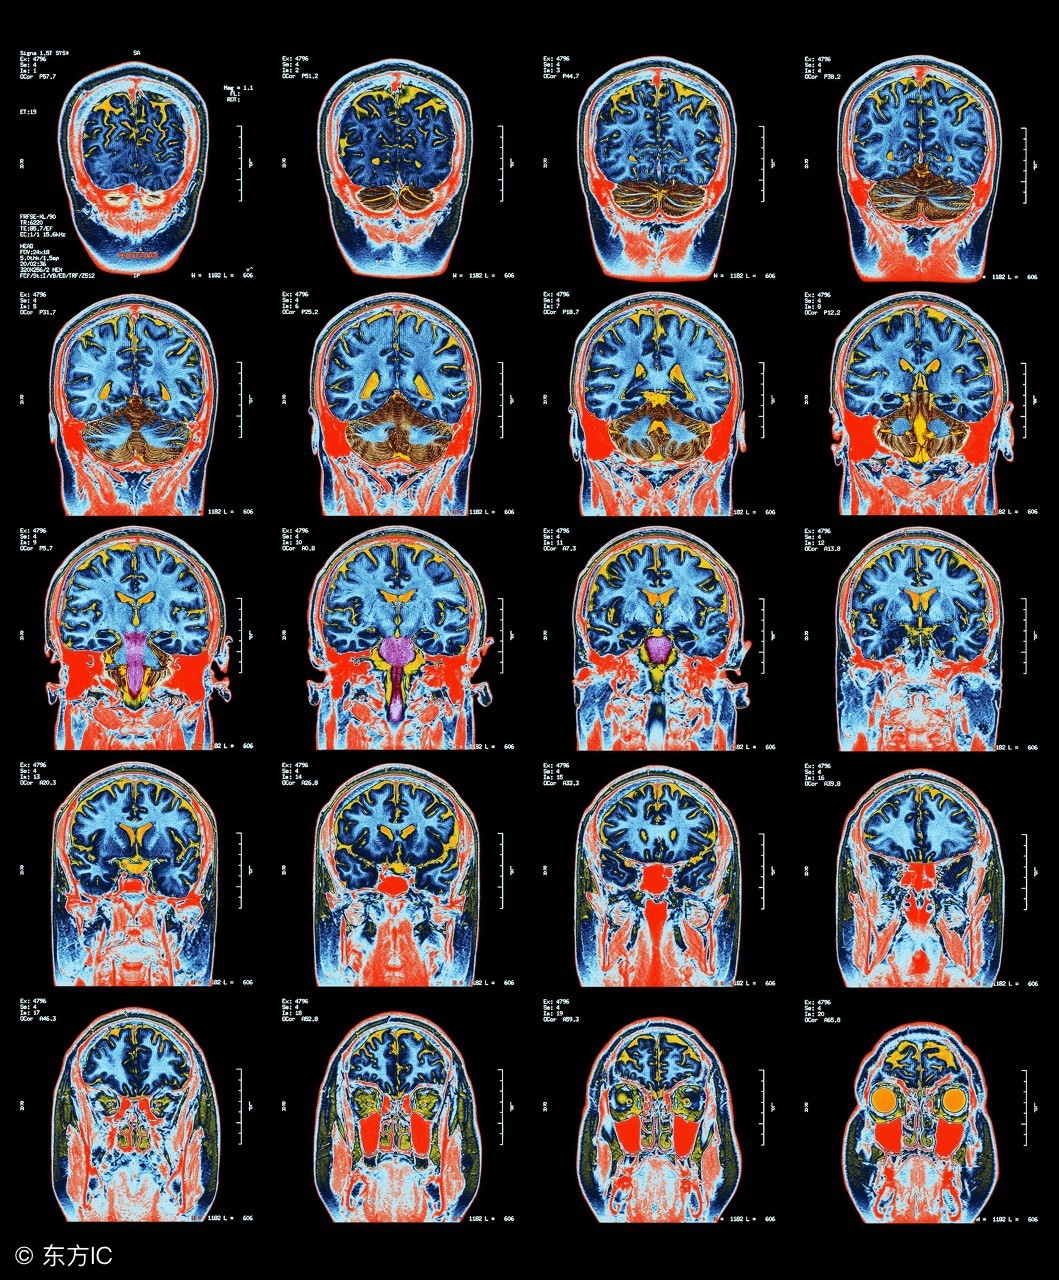

小脑萎缩的常见症状